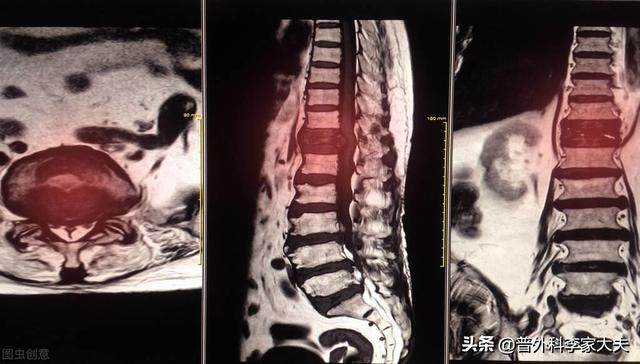

数日前、肺がんの骨転移の患者を診断したばかりで、彼の症状は長期的な腰背部痛で、彼らはいつも腰椎の筋肉の緊張、または腰椎椎間板ヘルニアに苦しんでいると思ったが、気にしなかった、本当に痛みが深刻で、下肢の神経症状が現れ、唯一の検査のために病院へ、そのCT検査に与えられた、明らかな椎骨破壊があることがわかった。......病歴を詳しく調べると、患者は長期的に咳の症状があるため、肺がんの骨転移が強く疑われ、肺のCT検査を行ったところ、主な焦点は......巨大な肺がんであることがわかった。

がんによる骨転移患者の痛みには一定の特徴がありますが、一般的な病気と干渉する症状も見受けられます。もし患者が発生した場合、脊椎の骨転移が神経を刺激し、医師や患者が椎間板ヘルニアによって誘発された症状を誤診しやすく、この時、患者として、体に異常があるため、適時に医師の助けを求め、医師として患者とコミュニケーションを図り、比較的質の高い検査を行い、骨転移のリスクを除外しようとする。例えば、高齢者の長期的な腰痛に対しては、レントゲン検査の代わりにMRI検査を行うことをよく勧める。例えば、慢性的な腰痛を持つ高齢者に対しては、レントゲン検査の代わりにMRI(磁気共鳴画像装置)検査を受けるよう勧めることがよくあります。

骨転移はどのような痛みに注意すべきですか?骨転移は悪性腫瘍の末期によく見られる症状で、体の他の部位にある原発腫瘍が血液やリンパ液の経路を通って骨に転移し、骨転移を形成することを指します。骨転移は、正常な骨組織が破壊され、腫瘍組織に置き換わっていることを示す。骨転移は病変の特異性により、溶骨型、造骨型、混合型の3つに分類される。骨転移の好発部位は中軸骨(脊椎、骨盤)、肋骨、下部骨幹部で、特に中軸骨が最も多く、これはこの部位の血液供給の特徴と関係しています。下の円のように骨転移が多発し、脊椎の状態が悪い。

胸椎に発生した骨転移性癌を示す。